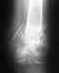

Прошу Вас посмотреть результаты КТ (сделана 07 ноября; травма была 23 октября), и если возможно, высказать Ваше мнение.